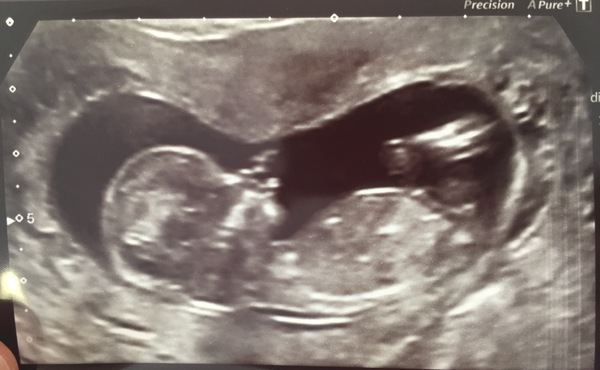

Everything fine! Very wriggly bambino inside with two arms, two legs and plenty of wavy fingers Smile

Due date now 1st April Grin

Great scan picture Celen!!

Lovely scan pic, Celen.

Lovely scan pic Celen

Beautiful scan pictures ladies!!